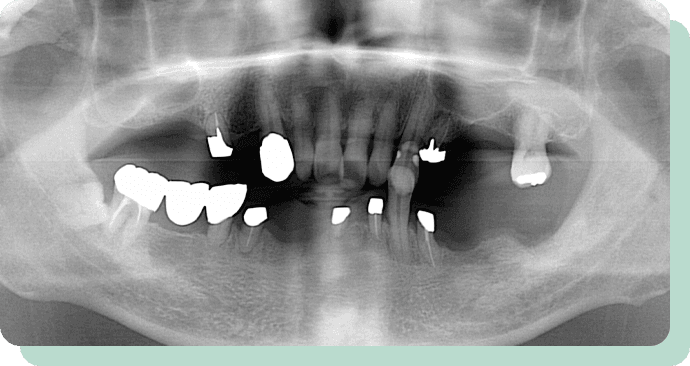

処置前後

左の写真は、歯周病が進んで、どんどん歯が抜けていっている状態です。

この方は、歯を短くし、金属のキャップの上に特殊な入れ歯を装着。

これにより、快適にお食事ができるようになりました。